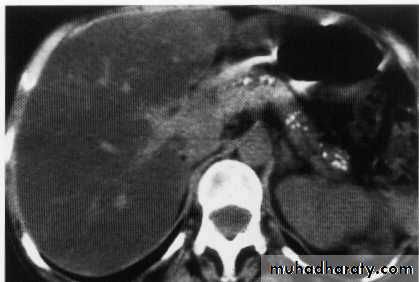

Hepatic mets.

FNH